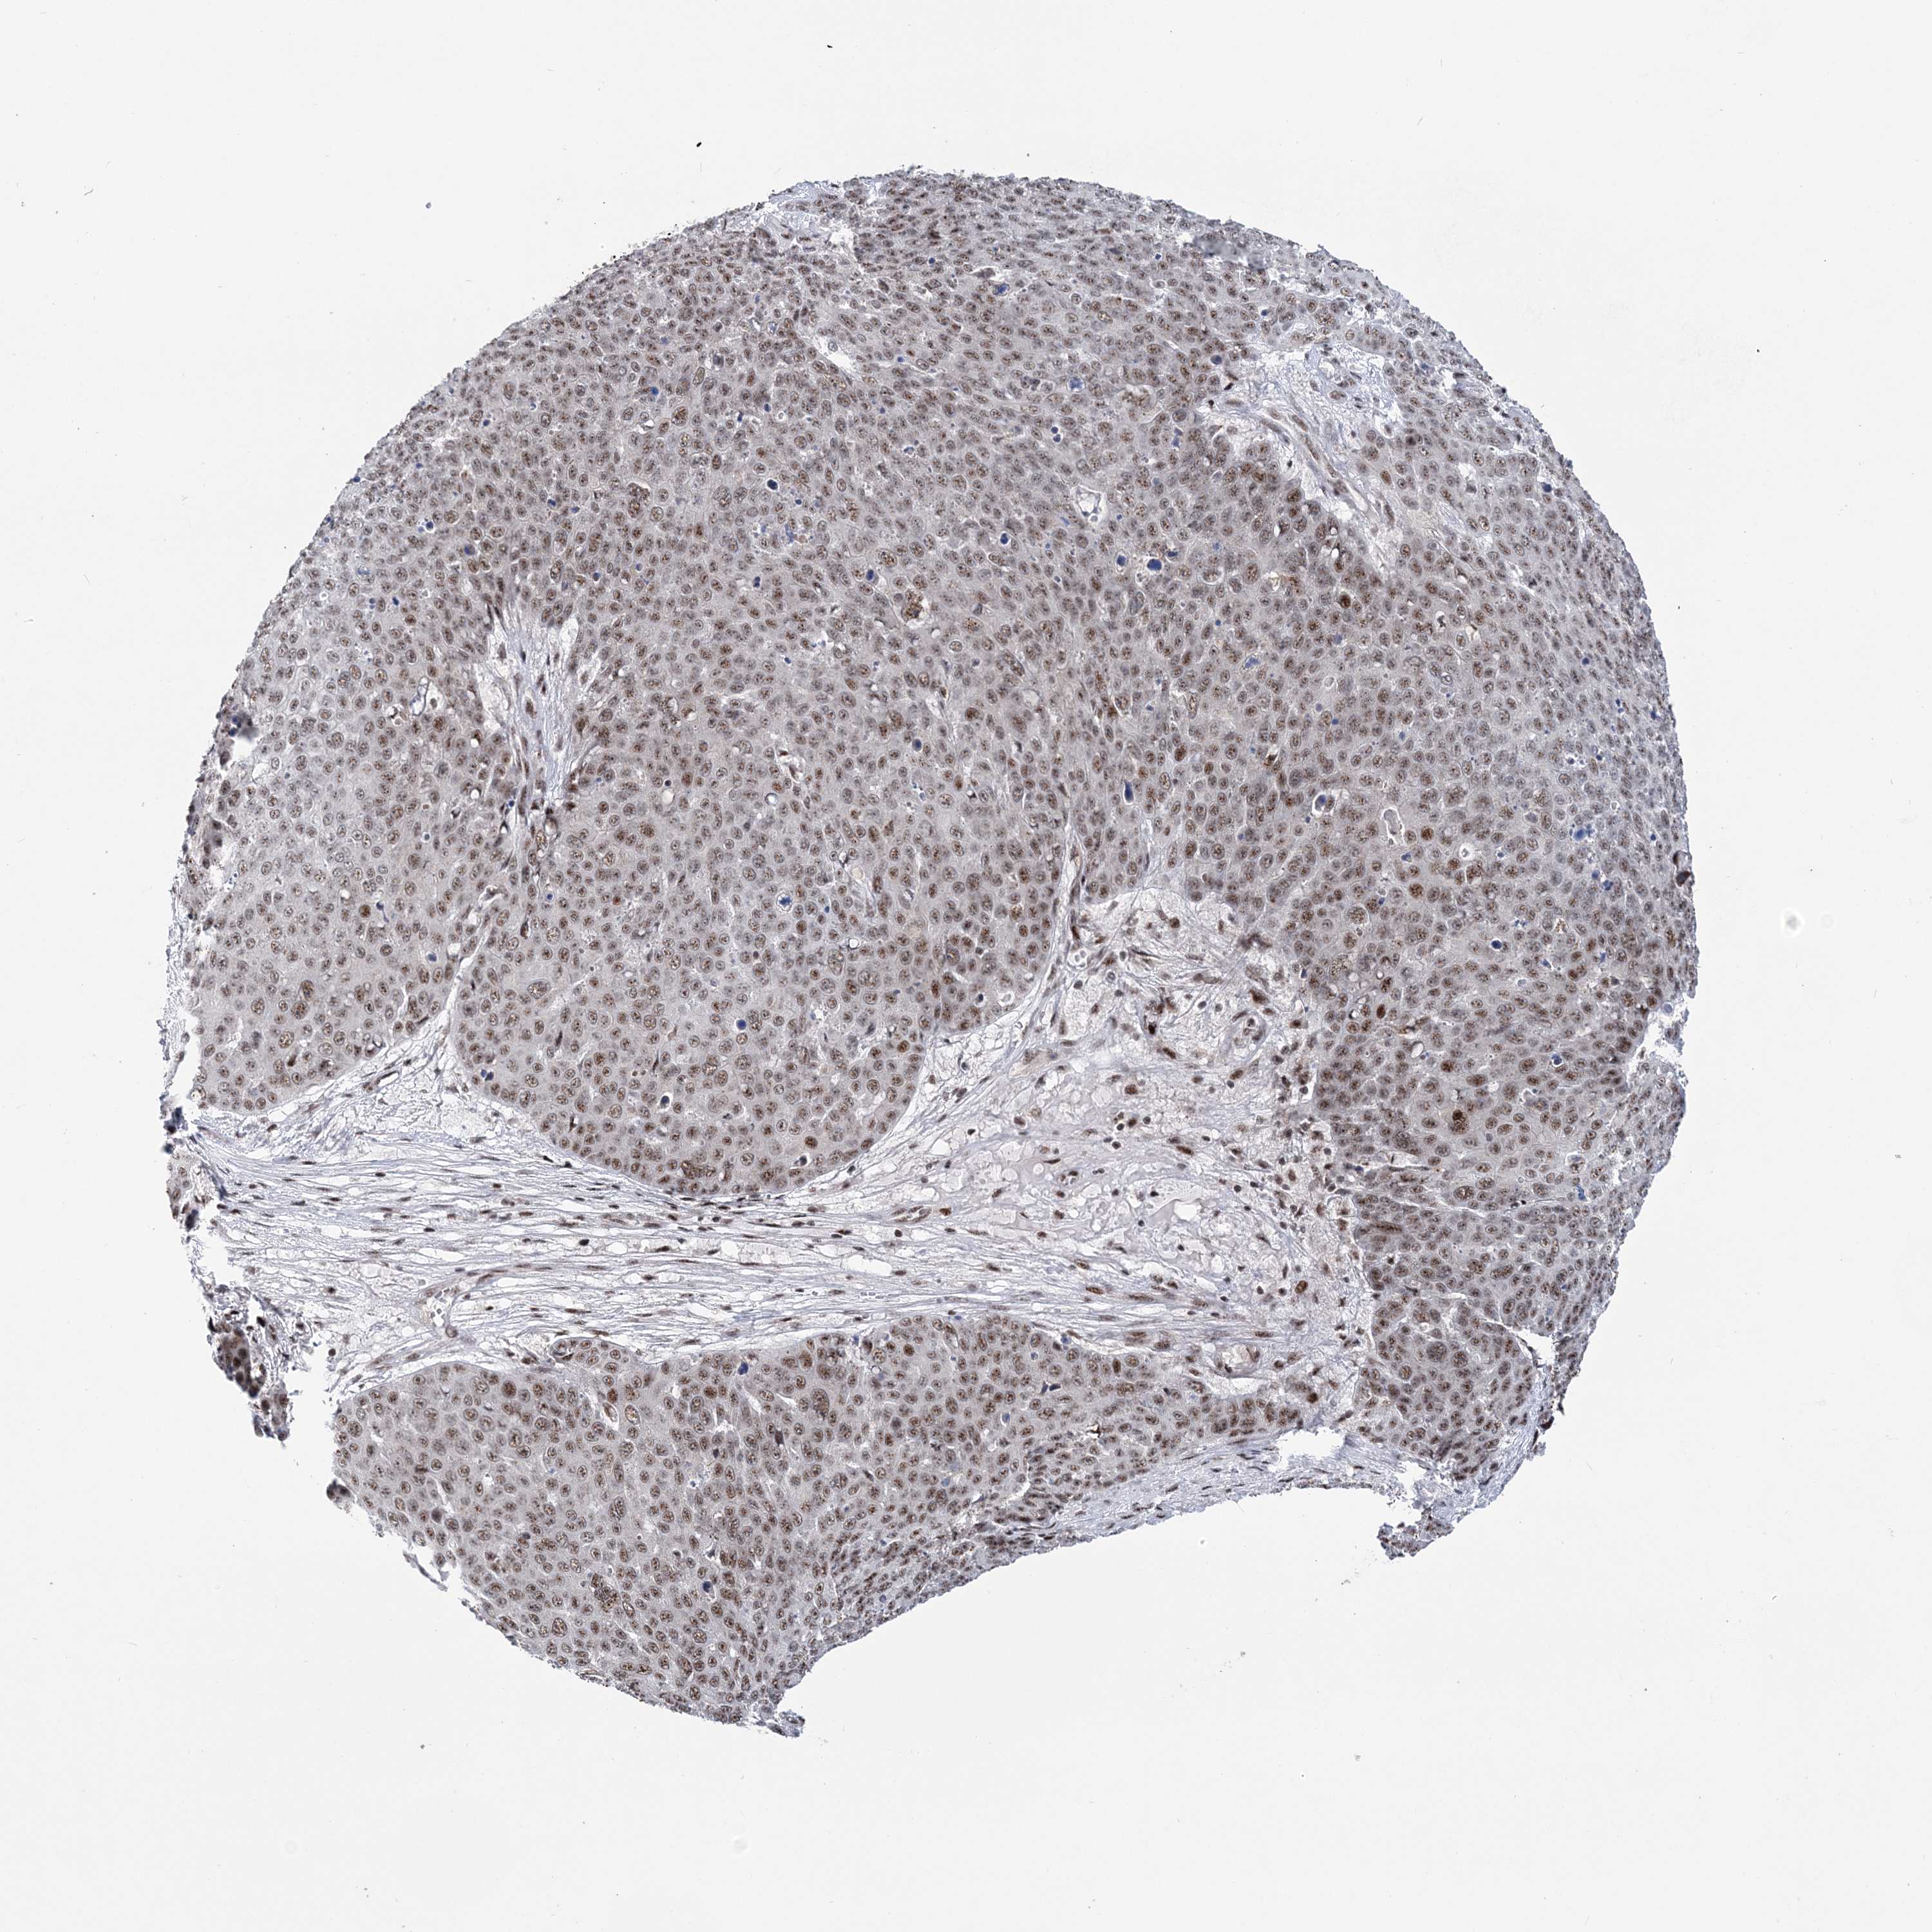

SKIN CANCER - Protein expressioni

A mouse-over function shows sample information and annotation data. Click on an image to view it in a full screen mode. Samples can be filtered based on level of antibody staining by selecting one or several of the following categories: high, medium, low and not detected. The assay and annotation is described here.

Antibody stainingi

Antibody staining in the annotated cell types in the current human tissue is reported as not detected, low, medium, or high, based on conventional immunohistochemistry profiling in selected tissues. This score is based on the combination of the staining intensity and fraction of stained cells.

Each image is clickable and will lead to virtual microscopy that enables deeper exploration of all samples and also displays staining intensity scores, fraction scores and subcellular localization as well as patient and tissue information for each sample.

Antibody HPA036822

Staining

High

Medium

Low

Not detected

Intensity

Strong

Moderate

Weak

Negative

Quantity

>75%

75%-25%

<25%

None

Location

Nuclear

Cytoplasmic/membranous

Cytoplasmic/membranous,nuclear

Basal cell carcinoma